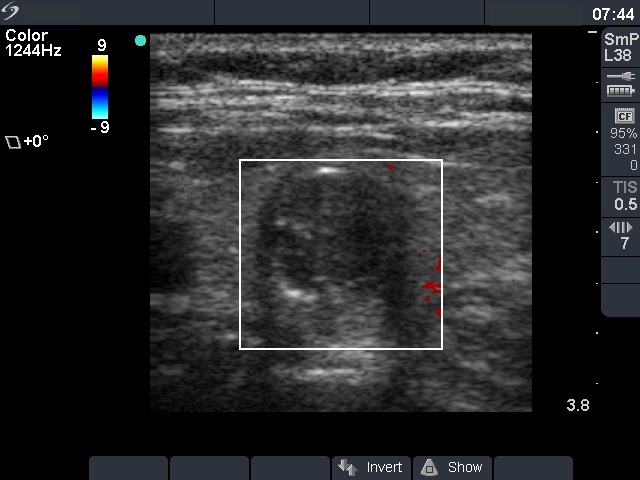

Ultrasonography. The thyroid was echonormal. There was a minimally hypoechogenic nodule in the right and a hypoechogenic nodule in the left lobe. The latter presented the so-called eggshell calcification.

Ultrasonography: The ultrasound presentation of the thyroid was unchanged.

The volume of the nodule was 1.15 mL and 1.43 mL, at the first examination and at the 4-year follow up, respectively. It means a 24% increase in volume which is beyond the intraobserver variation.Aspiration cytology was repeated and resulted in benign follicular proliferation.